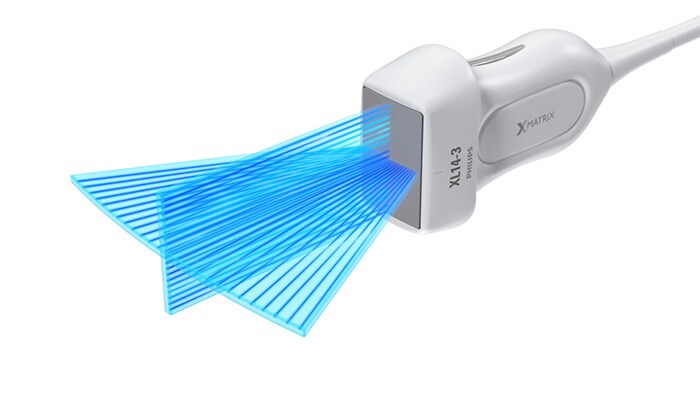

El primer transductor de array lineal xMATRIX del mundo

El transductor de array lineal XL14-3 xMATRIX para evaluaciones vasculares supone el mayor avance en 20 años de los ultrasonidos vasculares.

Array lineal XL14-3 xMATRIX

El transductor XL14-3 xMATRIX incorpora la impresionante cifra de 56 000 elementos, todos ellos conectados a un microcanal independiente. El transductor XL14-3 cuenta con enfoque electrónico multidimensional para adquirir imágenes de cortes ultrafinos de la anatomía vascular y la morfología de la placa. La ventaja principal: una excepcional de diagnóstico fiabilidad durante la evaluación de la estenosis y de la placa vulnerable.